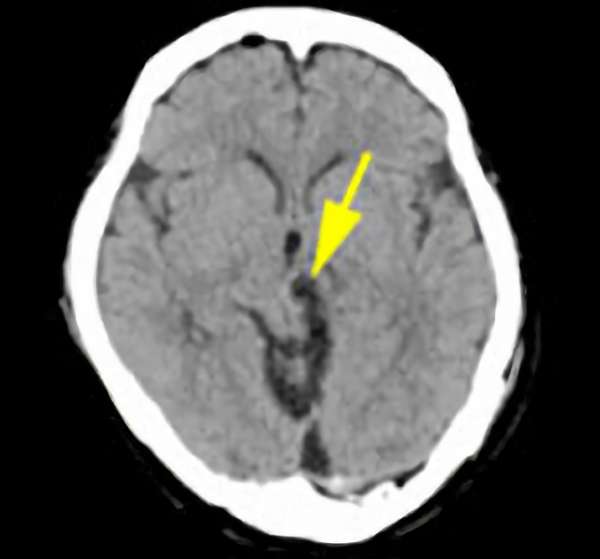

脳幹部

海綿状血管腫

出血の予防目的

熊本県の病院

No.No.62 手術前1

No.No.62 手術前2

No.No.62 手術後1

No.No.62 手術後2

CT/MRにより完全に摘出されたことが確認された